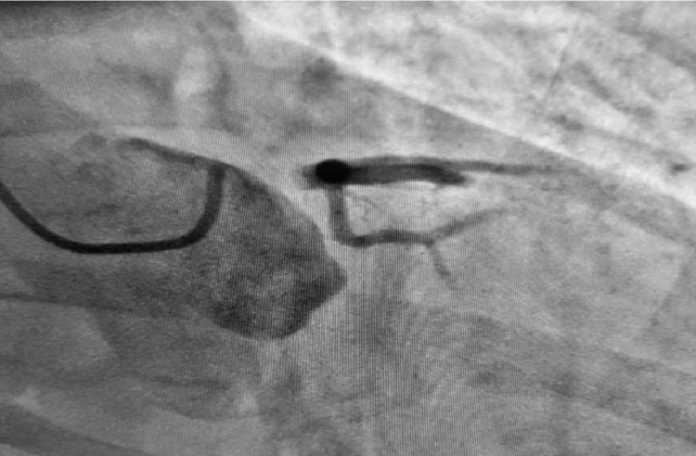

Интраоперационно кардиолог совместно с эндоваскулярным хирургом и кардиохирургом приняли решение о проведении стентирования ствола левой коронарной артерии. Учитывая стабильные показатели гемодинамики пациента, отсутствие кардиогенного шока и отёка легких, решено воздержаться от механической поддержки кровообращения (внутриаортальной баллонной контрпульсации). Оперативное вмешательство прошло без особенностей, по окончанию стентирования ширина просвета ствола левой коронарной артерии полностью восстановлена, достигнут кровоток TIMI 3 (рис. 3).

Рис. 3. Коронароангиография: восстановление кровотока по левой коронарной артерии. Fig. 3. Coronary angiography demonstrating restoration of blood flow in the left main coronary artery.